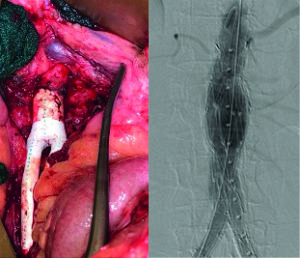

He continued: “We’ve looked at our institutional experience, which, again, is relatively small and modest compared to many, but it has decent, moderate follow-up—36-months in our study. We tried to cohort patients who were similar. If you look at demographics between patients, they really aren’t dissimilar, so we are trying to do an apples-to-apples comparison. We are also going to perform a subgroup analysis on the TASC C and D lesions, the more complex lesions. That was a significant difference between studies: Most of the unibody endografts, or UBEs—the Endologix device—were more TASC A and B patients, with fewer TASC C and D lesions, when compared to the aortobifemoral bypass graft. Obviously, this is a retrospective study; we certainly didn’t randomize these patients. This is operator preference.”

The study included 133 patients who had complete data, 82 of whom had AIOD only. Twenty one of these patients were treated with a UBE (26%), while 61 underwent aortobifemoral bypass grafting (74%). Significant differences in perioperative variables included surgery length (UBE: 213 minutes; bypass: 360), pre- and postoperative ankle-brachial indices (the UBE was lower than the bypass), and sizes of the iliofemoral arteries (larger in the case of the UBE).